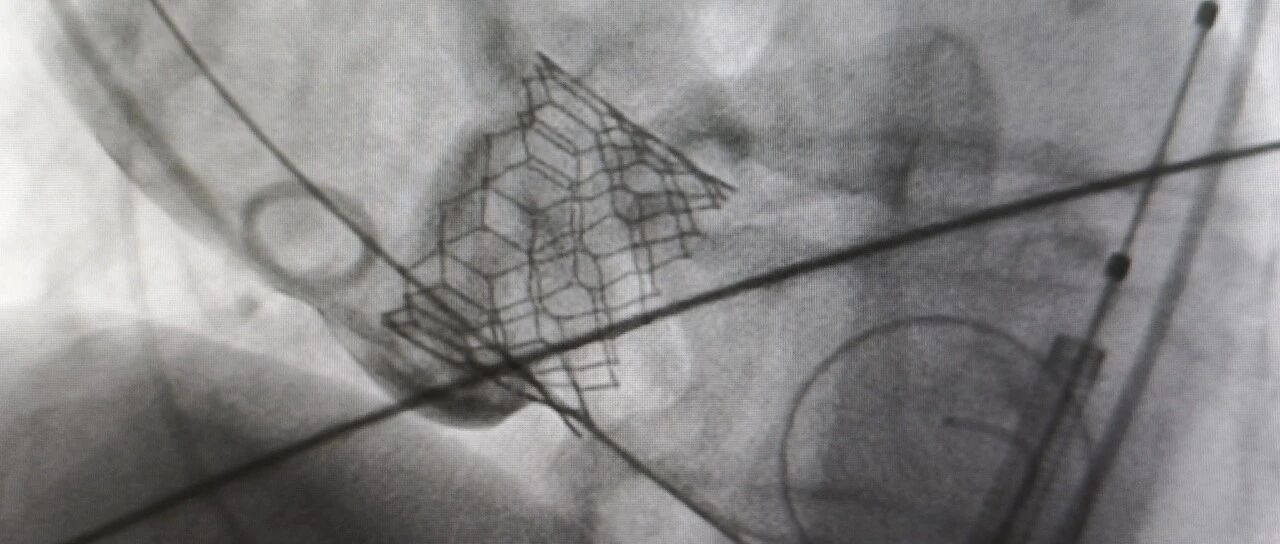

TAVI并发症-永久起搏器植入风险预测三要素